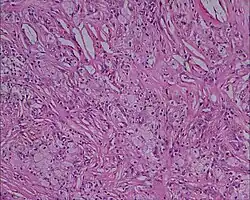

Xanthoma tuberosum

Xanthoma tuberosum (also known as tuberous xanthoma) is characterized by xanthomas located over tuberosity of the joints.[2]: 530